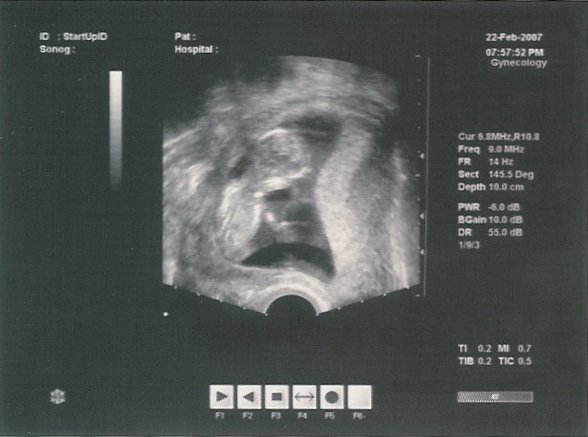

Én jövőhét csütörtökön megyek a 12.hetesre!!Nagyon izgulok!!

A tábliba:márc.1. 12hetes uh.